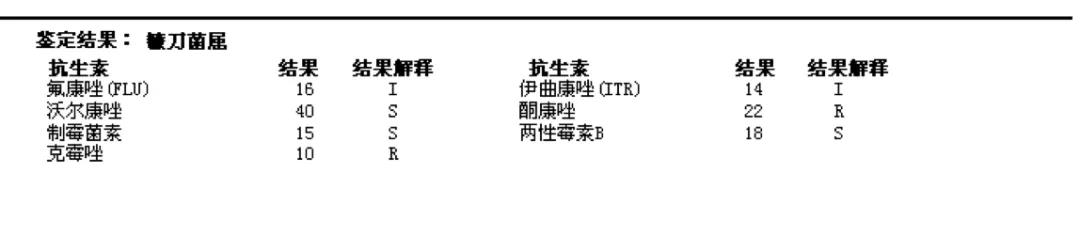

术中絮状物培养结果回报为:镰刀菌属(图13);病理提示符合真菌感染(图14)。

图14. 脑室内絮状物病理诊断:(脑室内)大量PAS染色+、PASM染色+的真菌菌丝及坏死物,符合真菌感染